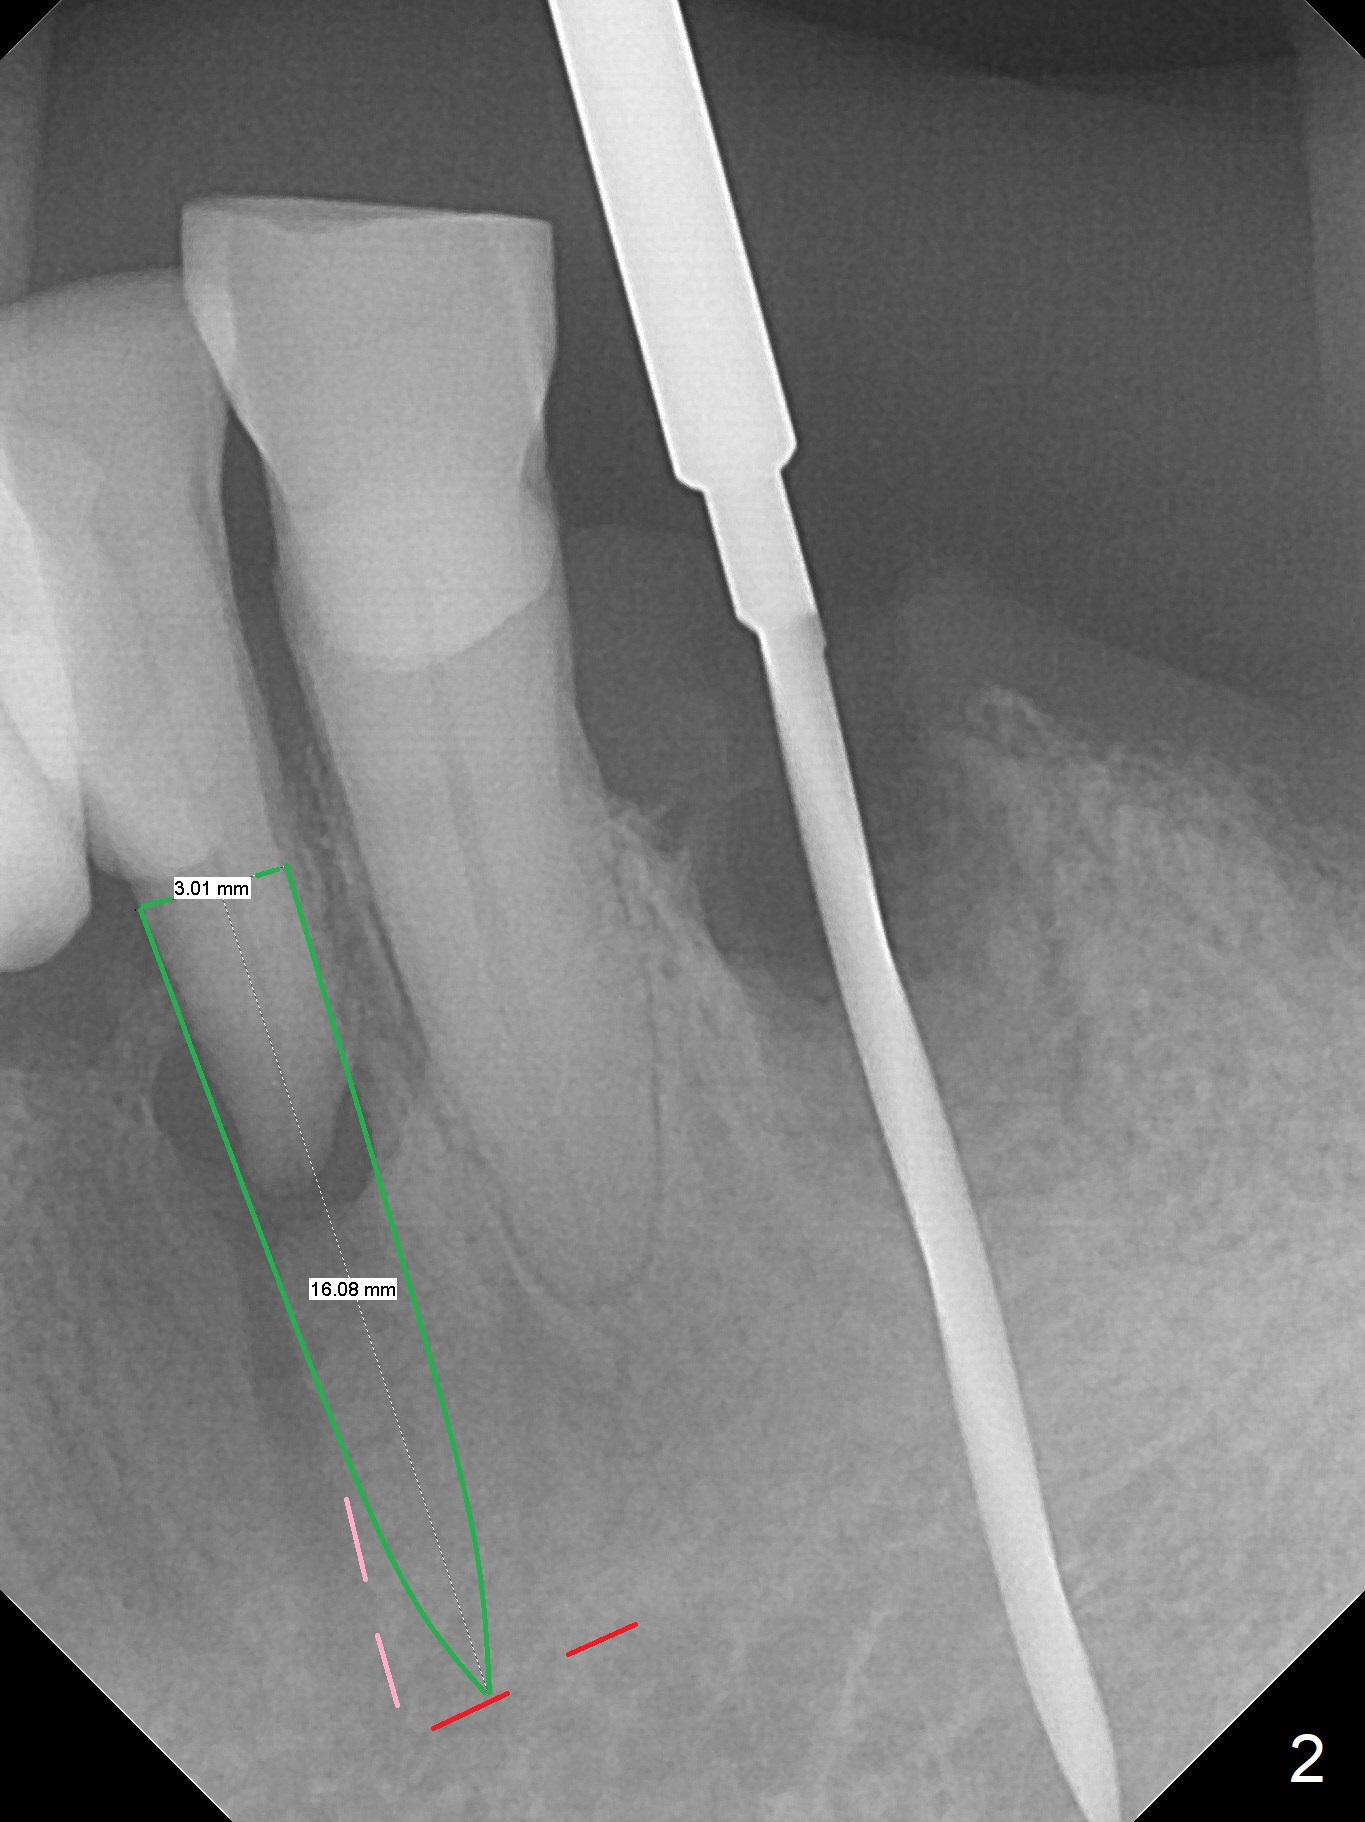

A 73-year-old man will return for #23 and 25 implants following ones at #21 and 31. Probably due to large periapical radiolucency at #23 (Fig.1 yellow dashed line), the terminal branch (pink) of the Incisive Canal (red) is distinct. Postop hemorrhage occurs associated with placement of a long implant at #. To prevent the complication at #23, a 14 mm long 1-piece implant (Fig.3) seems to be safer than 16 mm one (Fig.2). Seven mm in the native bone (Fig.3) should provide with sufficient primary stability. A temporary crown will be fabricated at #31. If the provisional at #21 is unstable, impression may be necessary for #21 and 31. Initiate osteotomy using visual and tactile acuity and double check the position and trajectory with RPD and X-ray. It might be preferable to extract the malpositioned incisor to give the remaining one the best 3-dimensional reference. Prepare 2 of 1-piece implant kits as well as angled one.